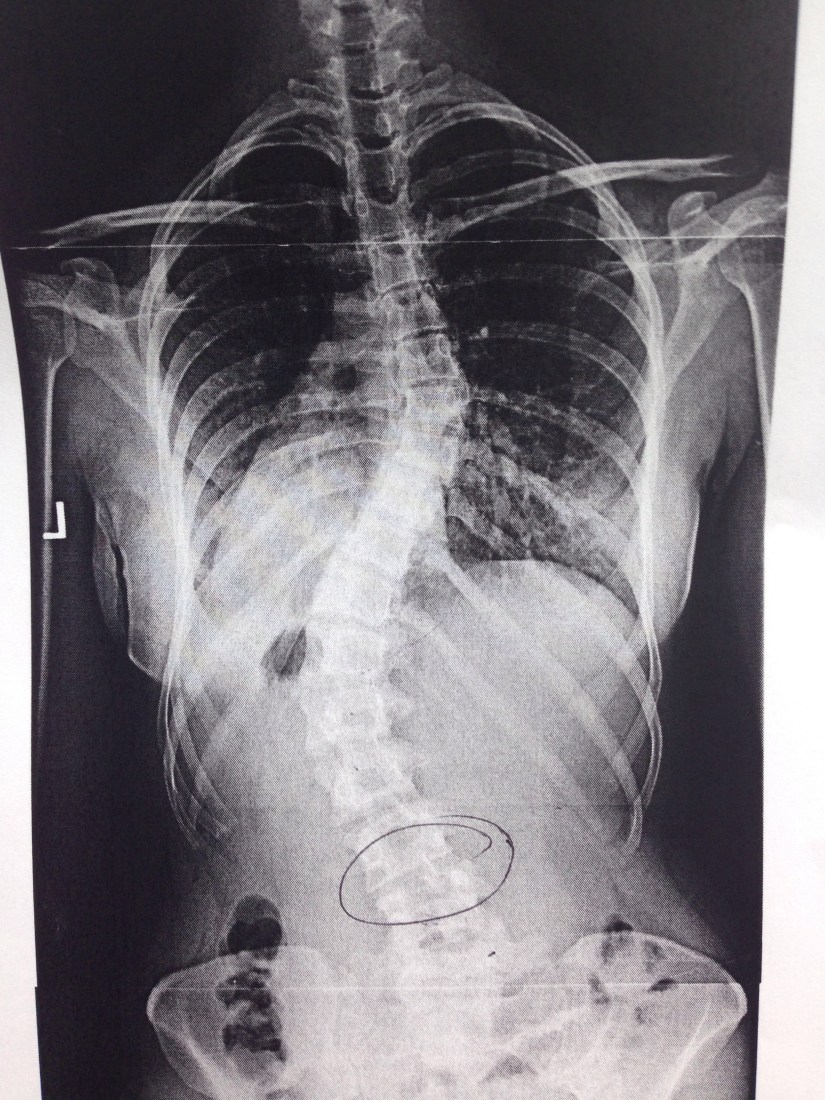

These days my main insecurity revolves around something that could have been prevented. I have pretty bad scoliosis. How I could have prevented it is a story for another time, all that matters is that I have it, it’s pretty bad, and it bugs me. I’m actually very lucky, I haven’t had issues with pain since high school so it really could be a lot worse. I do yoga, Pilates, get yearly x-rays, and basically do everything I can to maintain core strength to help keep it that way. On a daily basis I don’t really notice it, no one does. Most people don’t even realize I have it until I bring it up. But somehow I still find myself holding back tears sometimes when a Yoga instructor calls me out during class, a X-ray technician mentions how “crazy curved” my back is, or a new doctor wants to “make sure I know” that I have “severe scoliosis.” (like… duh. Ha come on!)

Sometimes I feel shame and embarrassment when someone notices my scoliosis without me mentioning it. It’s like my own dark little secret that I want to have complete control over so when someone else notices it, I am pretty caught off guard. A lot of time in Yoga instructors will be very hands on. They basically walk around and help students stay in correct alignment and deepen their practice. This is probably the hardest thing for me. I hate when the instructor comes to me. More often than not they notice my scoliosis and then offer alternative moves that might be easier for me. I think that’s where the shame comes in. I don’t want to be different; I don’t think anyone really does. I want to be able to do everything everyone else does and I take a lot of time and energy doing so. So when someone calls me out I get embarrassed and feel like I have to defend myself. I am working on that though and am really trying to embrace my scoliosis these days. Open back anything is my jam and honestly over time I’ve come to realize that I can do everything everyone else is doing.